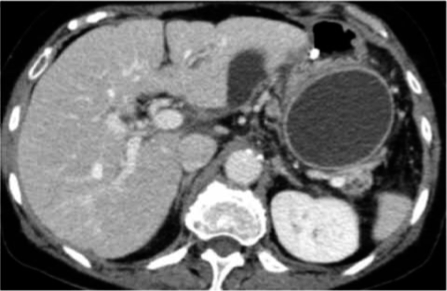

It is a collection of pancreatic secretions and inflammatory exudate enclosed in a wall of fibrous or granulomatous tissue. It is differs from a true cyst in that collection has no epithelial lining. It form commonly in the lesser sac near the pancreas and persist for 4 weeks or more from the onset of acute pancreatitis. It need drainage if it persists more than 6 week after the attack of pancreatitis , the size > 6 cm and symptomatic